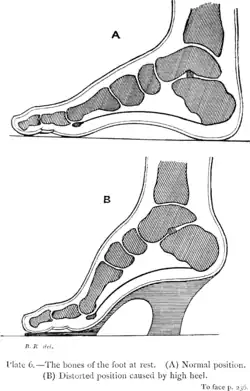

A 2001 survey conducted by Pennsylvania State University of 200 women found that 58% of women complained of lower back pain when wearing heels, and 55% of women said they felt the worst overall back pain when wearing the highest heel.[29] The same study argues that as heel height increases, the body is forced to take on an increasingly unnatural posture to maintain its center of gravity. This changed position places more pressure and tension on the lower lumbar spine, which may explain why some of the women complained of severe back pain at a higher heel length.

In a 1992 study, researchers from the University of California, Davis, and Thomas Jefferson University investigated the effects of increased heel height on foot pressure using forty-five female participants walking across a pressure plate in various heel heights.[30] A biokinetics software was used to analyze the exact pressure locations on and along each participants' foot. The researchers concluded that an increase in heel height leads to an increase in pressure beneath each of the metatarsal bones of the foot. Additionally, they found that the highest heel heights caused constant pressure that could not be evenly dispersed across the foot.

In a 2012 study, Kai-Yu Ho, Mark Blanchette, and Christopher Powers investigated the impact of heel height on knee stress during walking.[31] The study consisted of eleven participants wearing tracking and reflective markers as they walked across a 10-meter force-plated walkway in low, medium, and high heels. The study argued that as the height of the heel increased, the ball of the foot experienced an increase in pressure resulting in increased discomfort levels and peak patellofemoral joint stress. The researchers also mentioned that the long-term usage of high heels may lead to repetitive overstress of the joint, which may result in an increase in pain and, eventually, patellofemoral joint osteoarthritis and patellofemoral pain syndrome.

Plantar flexion of the foot in high heels

Plantar flexion of the foot in high heels